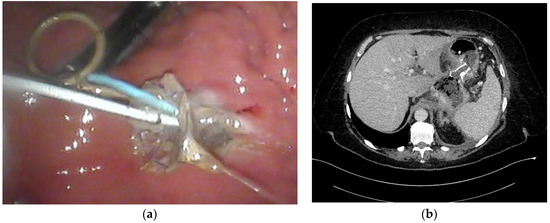

- Jagielski, M.; Smoczyński, M.; Adrych, K. Transpapillary drainage of pancreatic parenchymal necrosis. Wideochir. Inne. Tech. Maloinwazyjne 2015, 10, 491–494. [Google Scholar] [CrossRef]

- Smoczyński, M.; Jagielski, M.; Jabłońska, A.; Adrych, K. Transpapillary drainage of walled-off pancreatic necrosis- a single center experience. Wideochir. Inne. Tech. Maloinwazyjne 2015, 10, 527–533. [Google Scholar] [CrossRef] [PubMed]

- Smoczyński, M.; Jagielski, M.; Siepsiak, M.; Adrych, K. Endoscopic necrosectomy through the major duodenal papilla under fluoroscopy imaging. Arch. Med. Sci. 2018, 14, 470–474. [Google Scholar] [CrossRef] [PubMed]